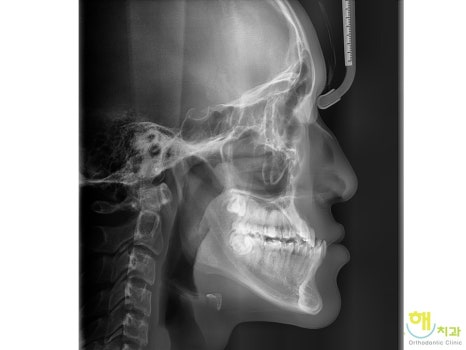

½ÉÇÑ ÁÖ°ÆÅÎÀ¸·Î º´¿ø¿¡ ³»¿øÇÑ È¯ÀÚ »ç·Ê

¼ºÀåÀ» Çϸ鼭

¾Æ·¡ÅÎÀÌ ³»³» ¾ÕÀ¸·Î ³ª¿Í

½ÉÇÏ°Ô ¹Ý´ë·Î ¹°¸®´Â Áõ»óÀ¸·Î

³»¿øÇÑ 16¼¼ ³²ÇлýÀÔ´Ï´Ù.

¹«·Á 6.5mm Á¤µµ

¾Æ·¡ ¾Õ´Ï°¡ À§ ¾Õ´Ïº¸´Ù ¾ÕÀ¸·Î ³ª¿Â

½ÉÇÑ ÁÖ°ÆÅÎ ÀÔ´Ï´Ù.